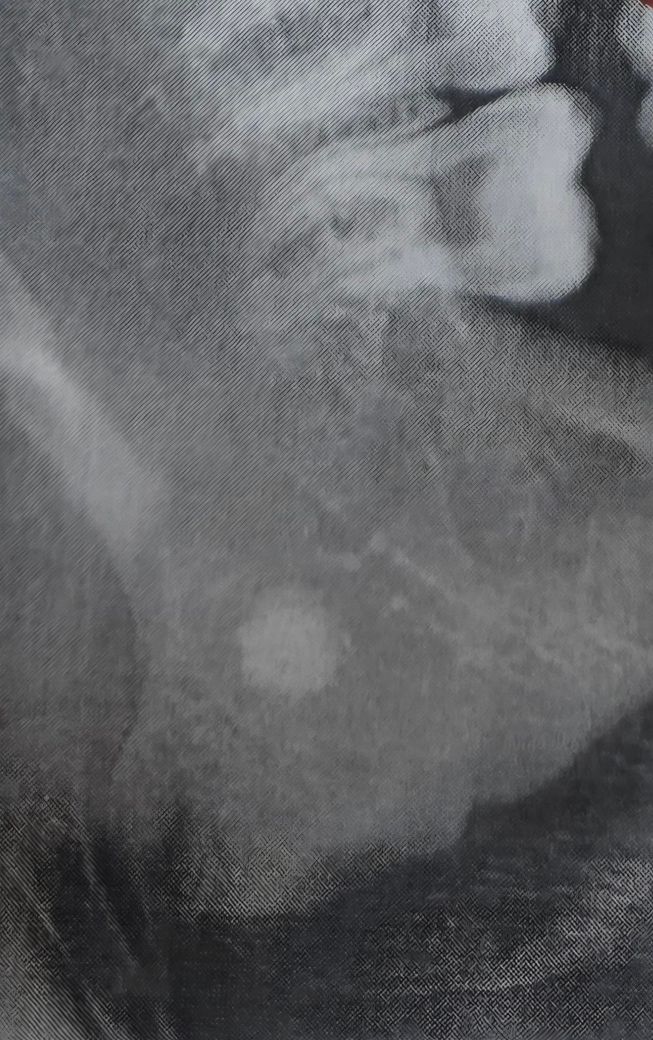

얼마 전 치과를 방문했는데 왼쪽 턱뼈 근처에서 흰색 동그란 게 발견되었습니다. 인터넷에 찾아보니 타석증일 수도 있다는데 병원을 가보는 게 좋을까요?

• 1번 째 사진

제공하신 엑스레이만으로 단정할 수는 없지만, 보이는 소견만 기준으로 설명드리면 다음 가능성을 고려합니다.

1. 타석증 가능성

침샘(특히 악하선) 타석은 엑스레이에서 비교적 경계가 분명한 원형 또는 타원형 고음영으로 보일 수 있습니다. 위치가 턱뼈 안쪽, 하악 하연 근처라면 타석증 가능성은 배제할 수 없습니다. 다만 모든 타석이 엑스레이에 보이는 것은 아닙니다.

2. 다른 가능성

림프절 석회화, 정맥 석회화(phlebolith), 치성 병변, 골내 석회화 병변 등도 유사하게 보일 수 있습니다. 증상이 없더라도 우연히 발견되는 경우가 흔합니다.